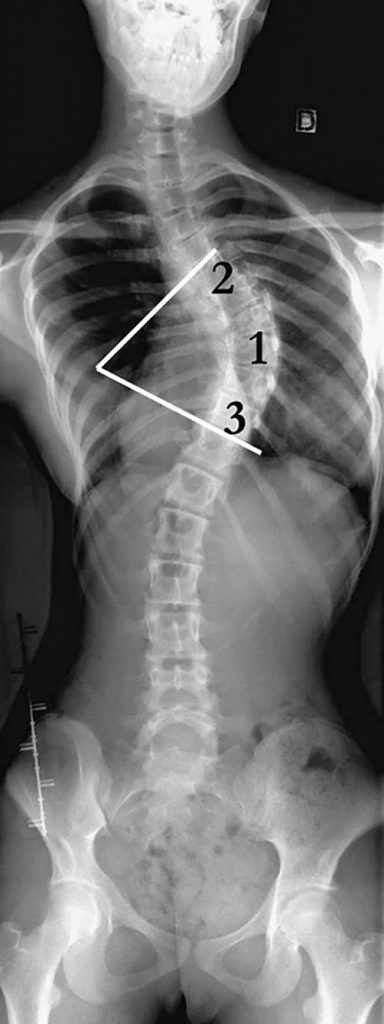

Examen clé du diagnostic, la radiographie d’ensemble du rachis est réalisée de face en position debout et de profil en position debout (figures 119.2 et 119.3).

Fig. 119.2 Radiographie du rachis de face debout.

Scoliose dorsale structurale idiopathique à convexité droite (le cliché est présenté « vu de dos » comme lors de l’examen clinique), centrée sur T8, vertèbre sommet (1) et allant de T5 à T10 : vertèbres limites supérieure (2) et inférieure (3), avec une rotation de la vertèbre sommet sur son axe (décalage de l’épineuse par rapport au centre du corps vertébral). Le bassin est horizontal. L’angle de Lipman et Cobb tracé sur le cliché quantifie l’importance de la scoliose.

Source : CERF, CNEBMN, 2022.